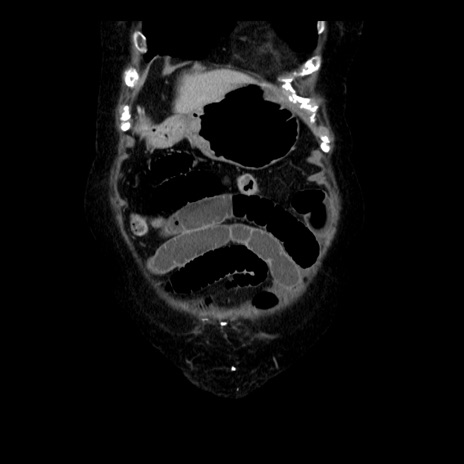

症例14(冠状断像)

【症例】 90歳代女性

【主訴】 腹痛・嘔吐

【現病歴】今朝から左側腹部痛を認めた。 経過観察していたが、嘔吐を認めたため来院。

【既往歴】 子宮癌術後

【身体所見】 意識清明、BP 127/54mmHg、P 98bpm Sp02 95%(RA)、BT 35.8°C、腹部平坦・軟腸ぜん動音聴取良好、右下腹部圧痛(+) 反跳痛なし

【データ】WBC 9800、CRP 0.46